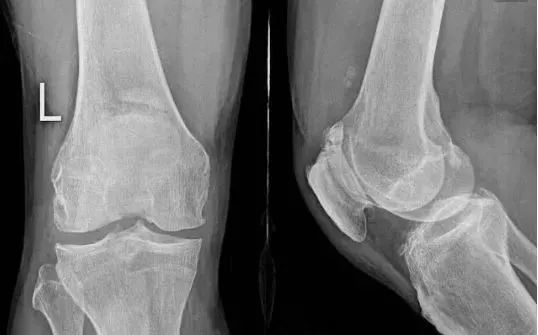

# 骨关节炎退行性(结果,非症状):

弹响低钝且频仍,响声发自骨外侧的髌股关节,同时伴关节肿胀,偶有交锁征象。MRI可看到关节退变,半月板呈“孤岛样”。关节镜下可看到关节软骨及半月板退变、骨质增生压迫韧带和关节囊。

# 髌股关节紊乱先赋性

平常见于支撑带挛缩、髁浅平、高/低位髌骨者。膝前弹响,声音清脆或低钝,频率高,伴有摩擦感或捻发音,髌骨勾当度差,髌周有压痛,研磨及阴抗试验都呈阳性。轴位片可以表示髌股关节适配差,正位片可以看到高/低位髌骨。关节镜可看到髌骨外倾或半脱位较多见,髌股关节面有软骨退变。

# 半月板问题

病因尚不了然,多继发于膝关节外伤,临床少见。弹响低钝,髌上囊或髁间窝可摸到质地坚硬的肿物,可能伴有关节交锁和屈伸受限。若是钙化严峻X光可以看到,MRI可以确诊。关节镜下可以看到滑膜增生、钙化,嵌顿于关节间隙,摩擦或撞击软骨。

病因不明,外伤时可诱发。弹响低钝,位置不确定,频率低,膝关节压痛弥散,伴关节肿胀,交锁少见。MRI可看到滑膜增生,呈结节状。关节镜下可看到滑膜充血增生,含铁血黄素沉积,侵蚀关节软骨和韧带。

外伤引起。膝关节不稳导致弹响,频率低且低钝,可伴有交锁,抽屉试验阳性。核磁可明晰诊断。关节镜下可看到韧带断端嵌于关节间隙,或有软骨损伤。